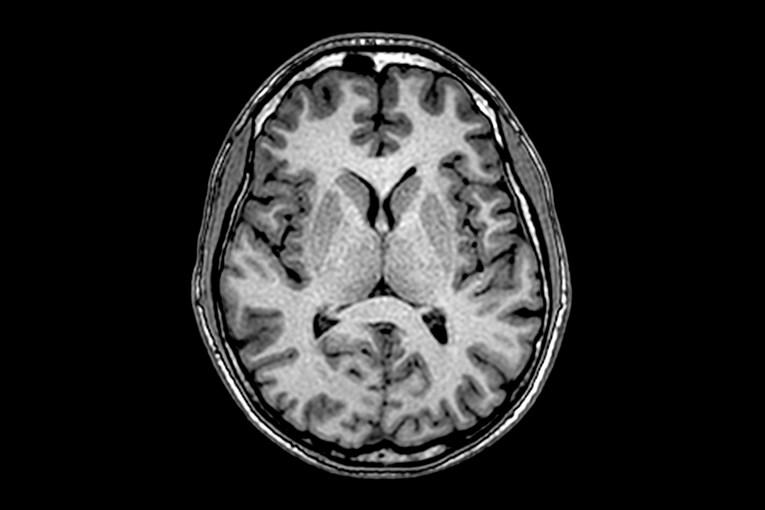

(Илустрација Shutterstock)